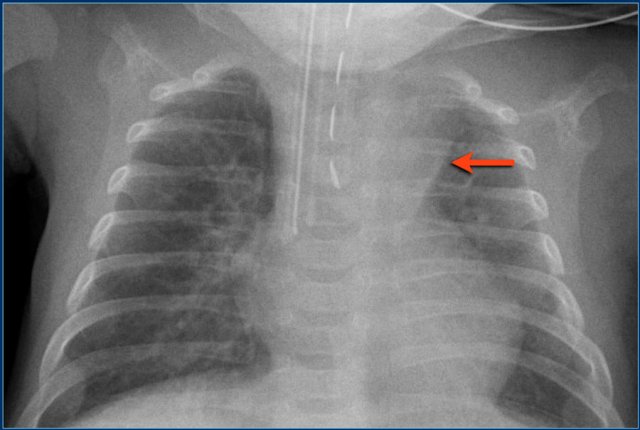

Endotracheal tube (4)

Study the image.

Then continue reading.

The findings are:

1. Endotracheal tube is positioned in the right main bronchus.

2. Atelectasis of left upper lobe of the lung.